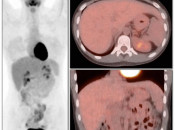

The normal liver demonstrates diffuse FDG uptake (typically greater than or equal to the spleen).

Many readers consider the uptake in the liver to represent the “background metabolic activity” for an exam.

For assessment of many lesions found in the body, the metabolic activity of the liver serves as the reference threshold by which to decide what is benign (uptake < liver) and what is malignant (uptake > liver).

Focal increased FDG uptake in the liver is always highly suspicious for malignancy. Very commonly, these malignant lesions may be poorly delineated on the co-registered CT images due to the lack of intravenous contrast administration.

Non-avid, low attenuation liver lesions are almost always benign (usually representing cysts, hemangiomas or fully treated malignant lesions), although some hepatocellular carcinomas can demonstrate only very mild metabolic activity.